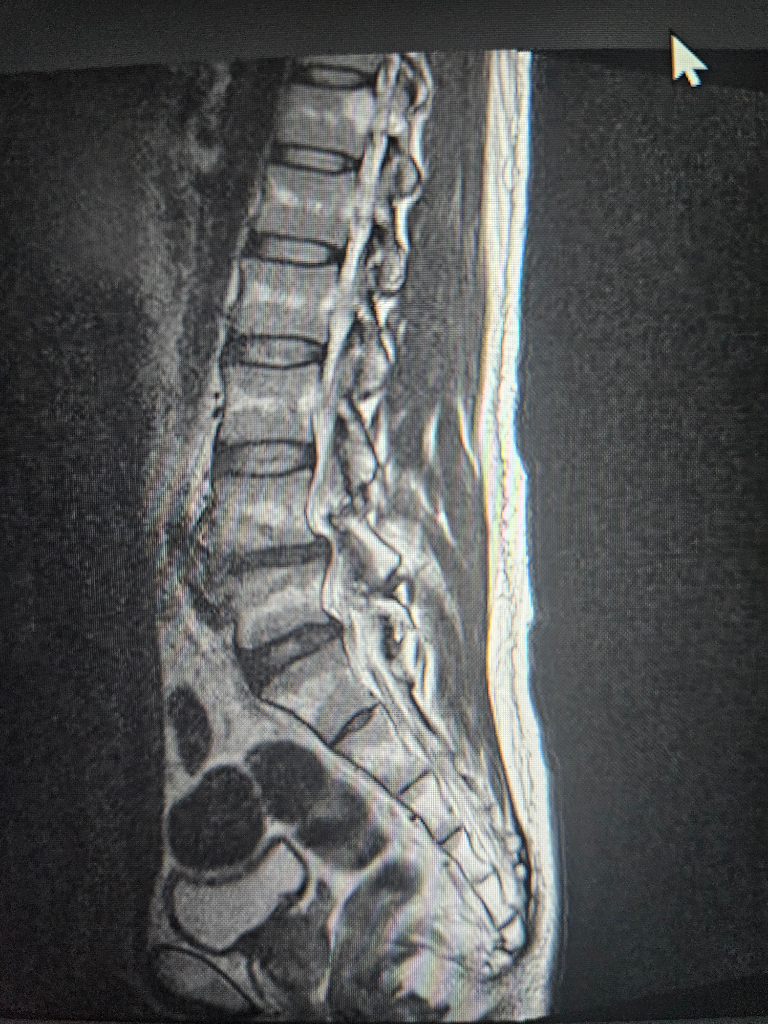

수술해야될 정돈지 사진보시고 확인좀 해주세요

척추분리증과 전방전위증등으로 통증이 너무심한데

허리부터 다리까지 통증이 있고 종아리까지 전기가 찌릿한 증상 누워있을때는 그나마 참을만 한데 그외 다른자세를 하면 통증이 심해집니다

걷는것도 10분이상하면 허리 부터 허벅지 까지 통증이 심하게 생깁니다

척추분리증은 30년 정도 되었고 다른건 10년이 넘은거 같습니다

약이나 물리치료도 오래 했지만 지금은 효과도 없고 시술또한 별다른 효과가 없어서 통증으로 인한 예민함과 잠잘때 힘이들어 정신과약을 복용중입니다

사진과함께 증상을 종합해봤을때 수술이 필요한지 아니면 보존치료가 더 나은지 궁금 합니다

보내주신 사진만으로는 정확한 진단을 내리기 어렵습니다. 정확한 진단을 위해서는 전문의의 진찰과 검사가 필요합니다. 하지만 사진과 증상을 종합해보면 수술을 고려해볼 수 있는 수준으로 보입니다.

척추분리증과 전방전위증은 척추뼈가 정상적인 위치에서 벗어나 발생하는 질환입니다. 이 질환은 허리와 다리에 통증, 저림, 감각 이상 등의 증상을 유발할 수 있습니다.

수술 방법은 여러 가지가 있으며, 환자의 상태에 따라 적절한 방법을 선택합니다. 일반적으로 척추뼈를 고정하는 척추유합술이 시행됩니다.

수술은 통증 완화에 효과적이지만, 합병증 위험도 있습니다. 따라서 수술을 결정하기 전에 전문의와 충분히 상의하여 수술의 장단점을 신중하게 고려해야 합니다.